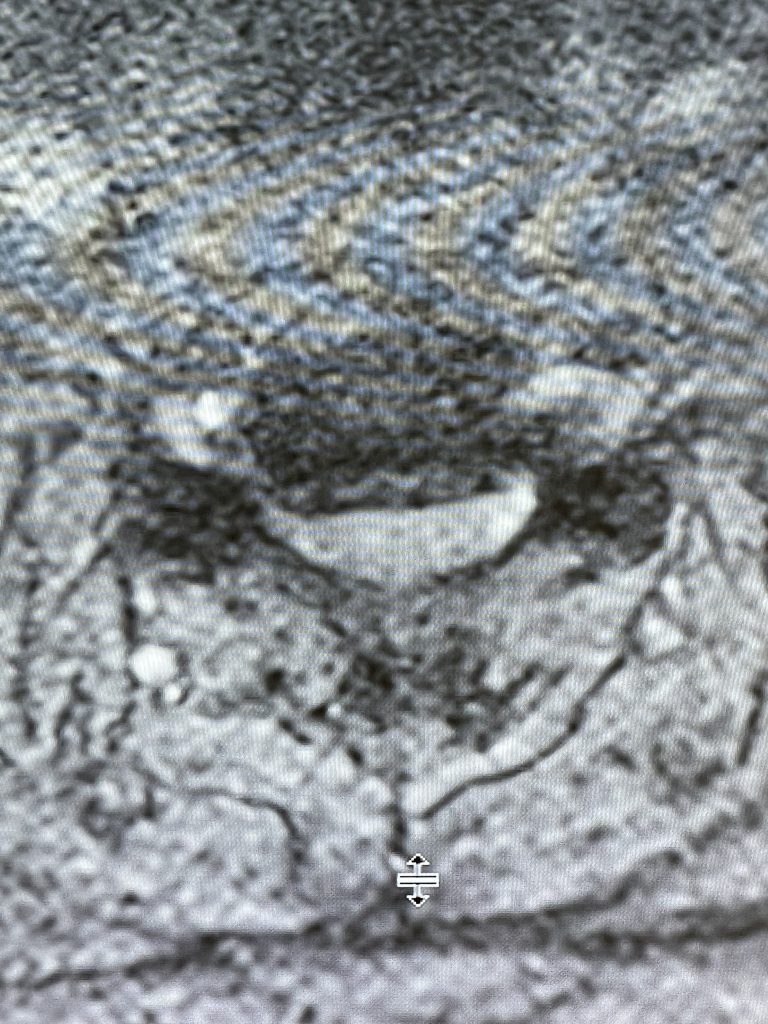

Nervous tissue is soft. The thecal sac is surrounded by a rigid bony ring which forms the spinal canal. Any mass that fills the very small […]